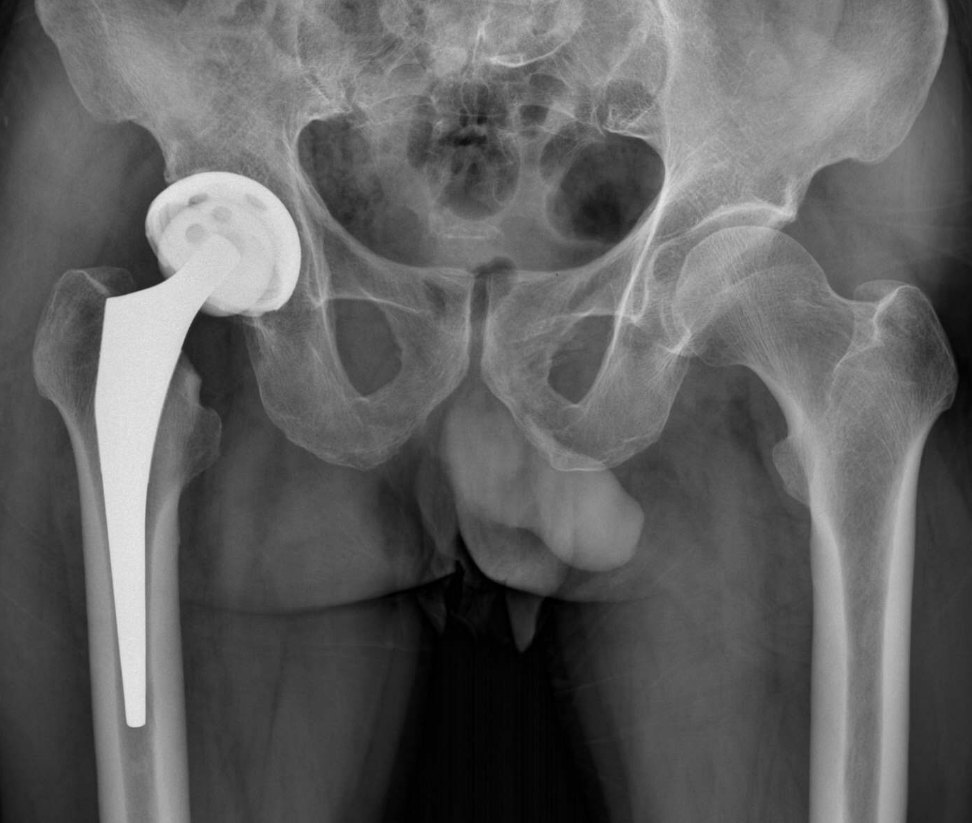

2、手術治療:對于嚴重骨頭壞死,可能需要進行手術治療,如骨移植、關節(jié)置換等,手術治療的效果因個體情況而異,需在專業(yè)醫(yī)生的指導下進行。